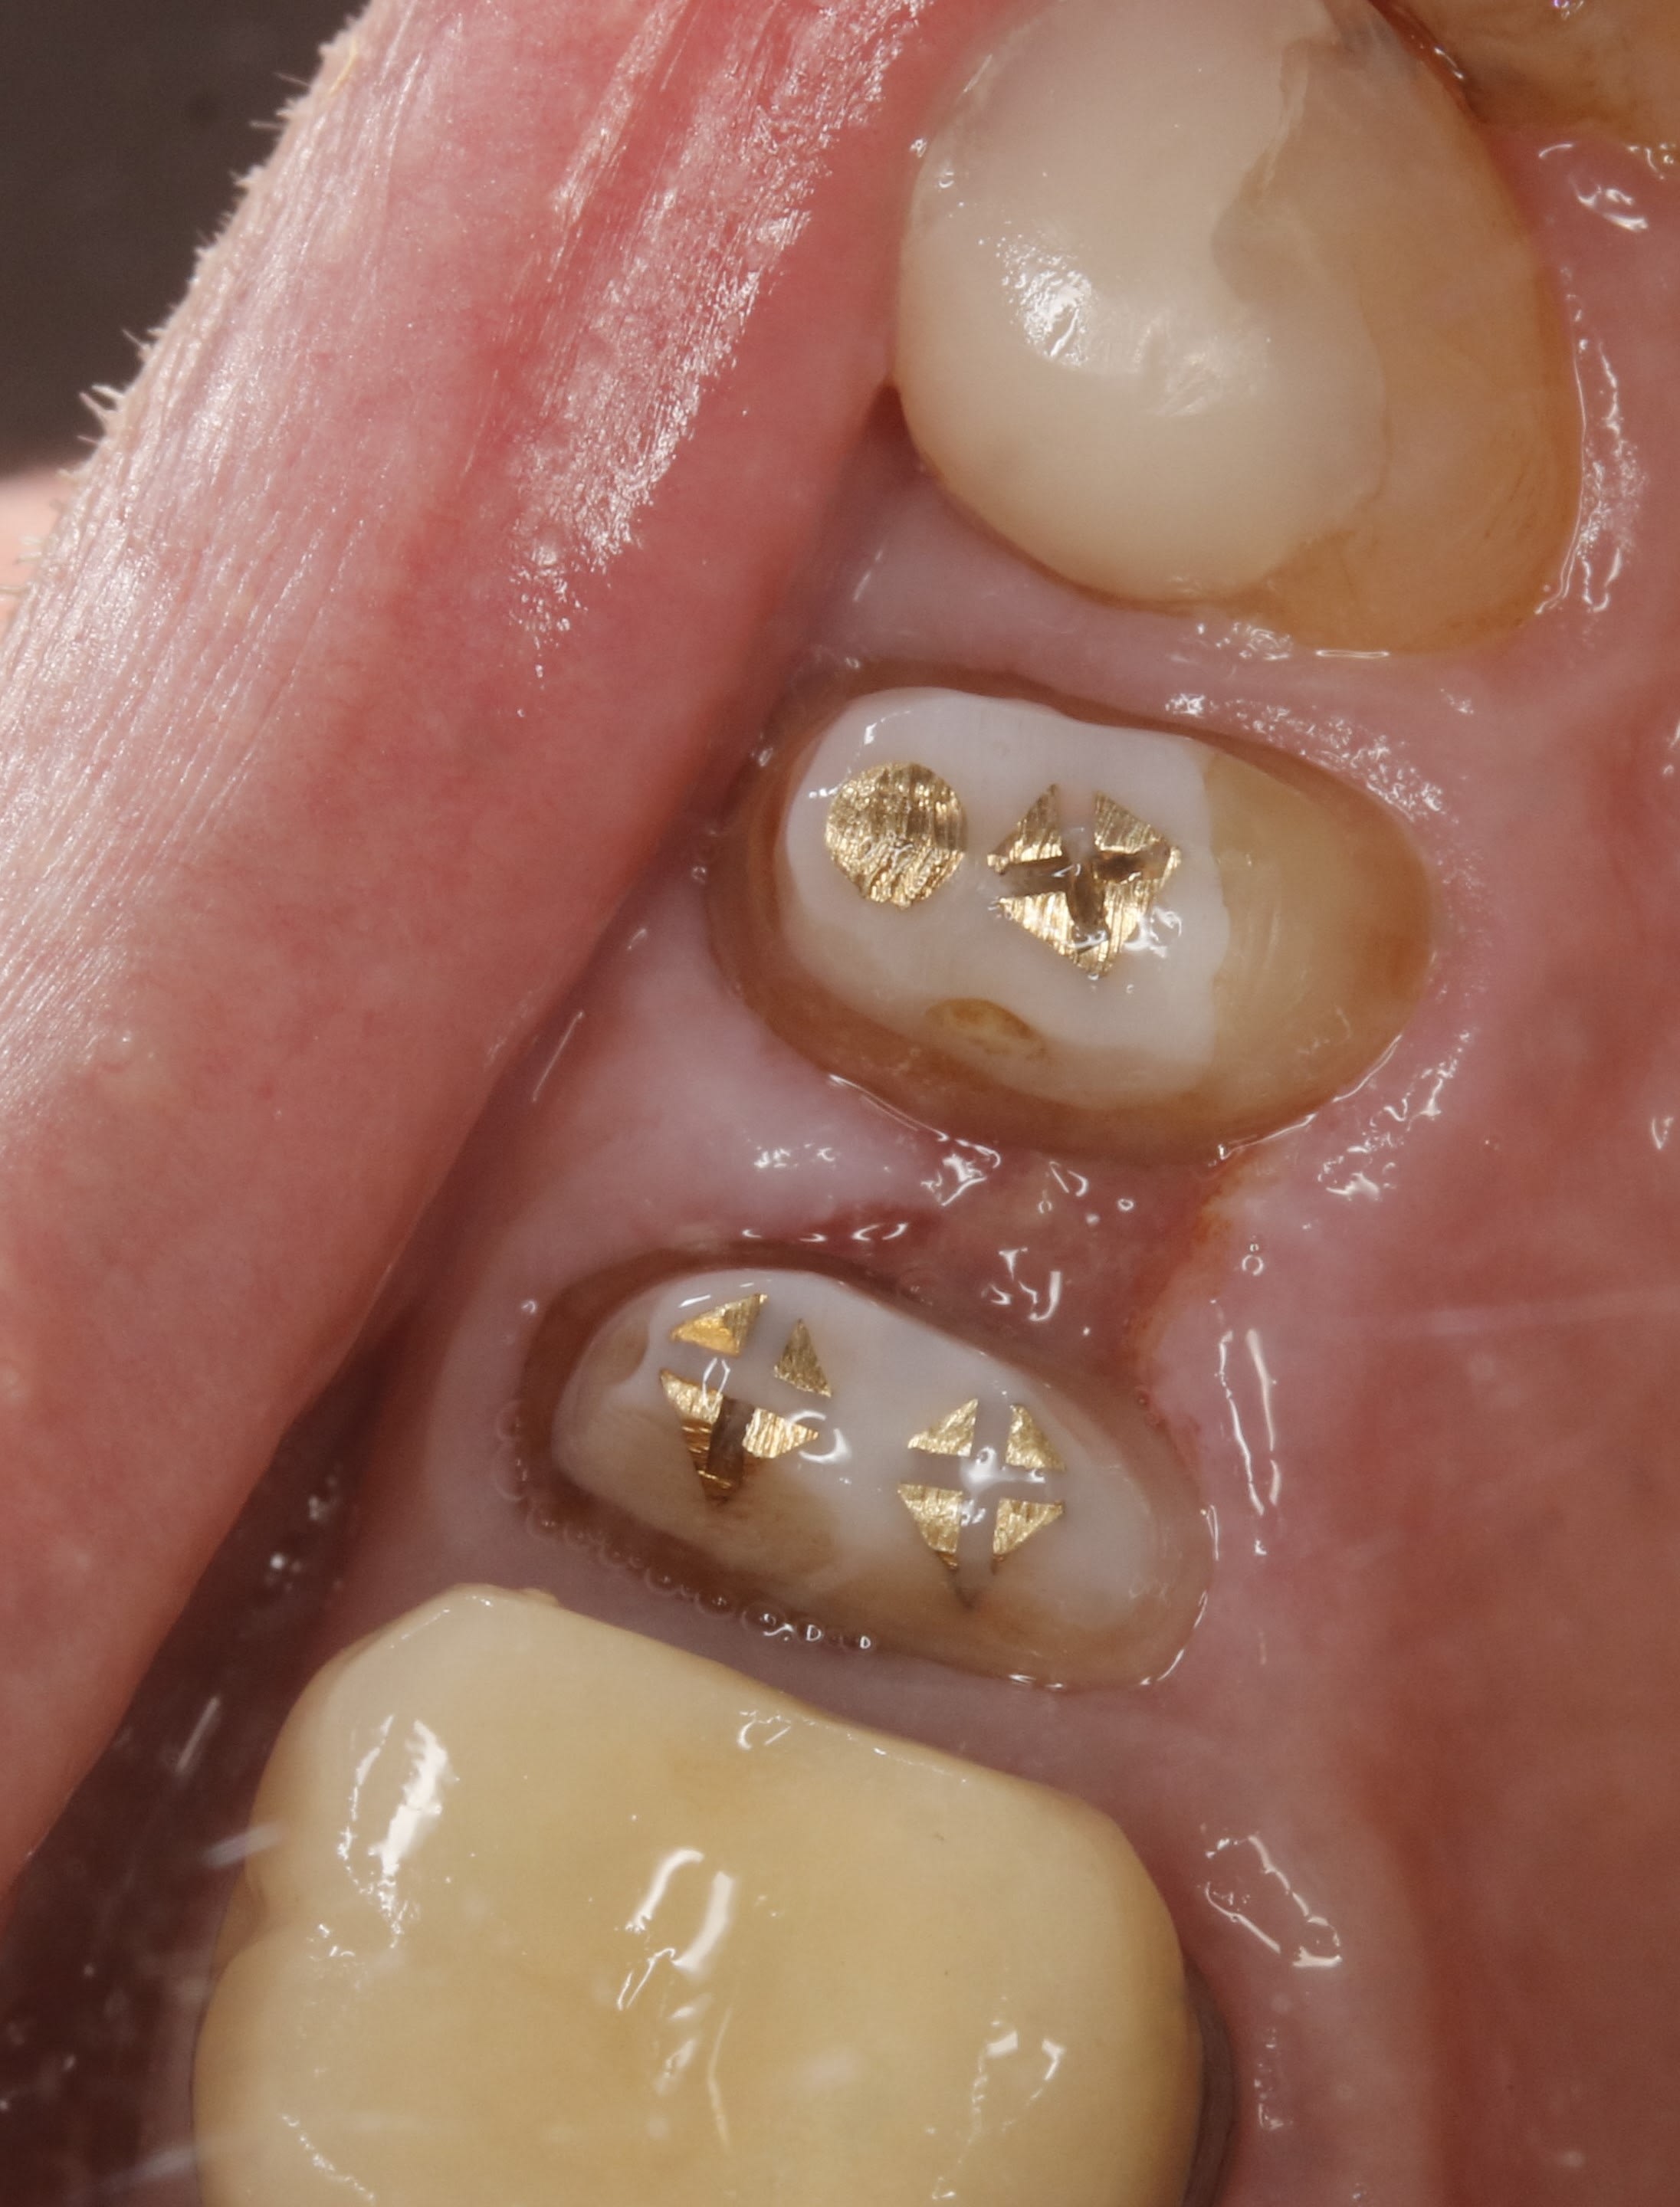

regardes celui là , je l avais dejà fraisé . j y met un peu de pate verte , et cela permet de reprendre la limite de la couronne .

la séance d après c est impec .

et après la couronne , aller hop envoyer 440 balles

lui il ressemble à la question du post , normalement il revient demain matin .

en principe , sans prov , ils n oublient pas :-)

on verra demain combien on a gagné .